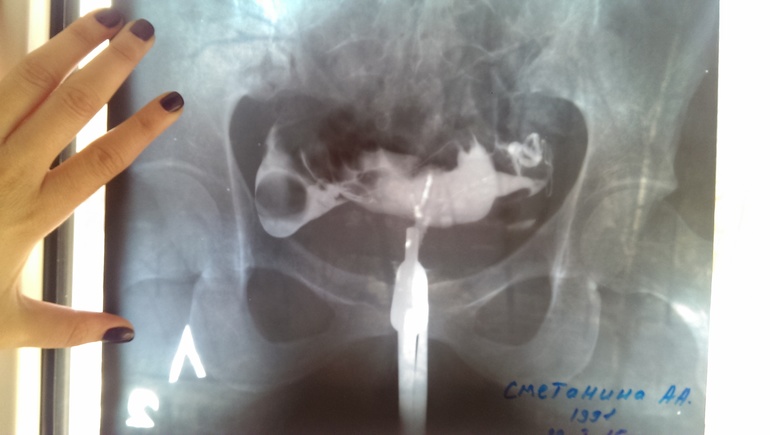

вышла женщина и говорит не беспокойтесь обе трубы проходимы...фуууф...я выдохнула...пошла сразу к Г...

его заключение:

матка сдвинута вправо из-за спаек малого таза,хоть трубы обе и проходимы,но права труба извилистая,ее можно считать бесполезной...сказал лапару делать мне нельзя,т.к много было операций и если туда опять залезть станет еще больше спаек. поэтому сказал в след.цикле отслеживать О именно в ЛЯ, и делаем ВМИ. сказал самим стараться бессмысленно-не получится,только время потеряем. дает 2-3 попытки ВМИ,если не дай Бог не получится-то на квоту ЭКО идем...вот такие новости! Я так рада,что все-таки сходила на МСГ,теперь хоть знаем,в чем проблема неудач и что нужно уже глобально думать! Фото под катом!